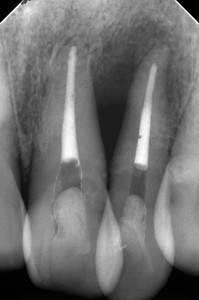

DB104821_150925142147(調整後)術前。21番22番を他院にて抜髄後、痛みが激しく当院に来院

小長谷先生が初診からずっと診ていらした方なのですが、動揺(++)自発痛(++)骨吸収(+++)みたいな感じで、かなり厳しい症例なようでした。

DB104822_151006171835(調整後)根充直後

痛みは落ち着いたようですが、骨吸収がかなり激しい・・・。

DB104821_160405183446(調整後)歯周基本治療終了後(SRP、再SRP)